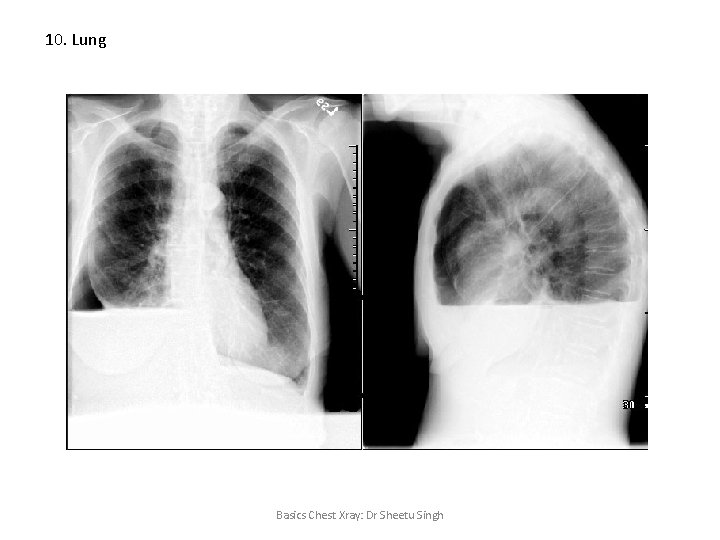

10. Lung Basics Chest Xray: Dr Sheetu Singh

10. Lung Pleural effusion • Obtuse angle with chest wall • Not confined to bronchopulmonary segment • Air bronchogram not visualized (seen in Consolidation) Diagnostic modality – I/L Lateral decubitus USG chest CT chest Basics Chest Xray: Dr Sheetu Singh